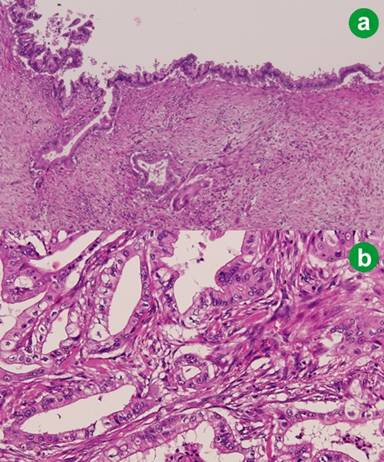

The patient returned to an oral diet on the 4th postoperative day. The postoperative course was uneventful and the patient was discharged on day 14 in generally good condition. The permanent pathologic report revealed an invasive mucinous cystadenocarcinoma with invasion to the common bile duct wall and peripancreatic soft tissue with regional lymph node metastasis (metastasis of 5 lymph nodes out of the 55 lymph nodes harvested) (Figure 3). He received UFT (tegafur) plus gemcitabine combination adjuvant chemotherapy and he is still alive. A follow-up CT at the 31st postoperative month showed a patent graft and no evidence of recurrence (Figure 4).

Figure 3. The permanent pathologic report revealed an invasive mucinous cystadenocarcinoma. a. Proliferating single layer of columnar epithelium with ovarian-like stroma. b. Infiltrating irregular dysplastic glands with stromal desmoplasia and irregular cell nests. (H&E; original magnification: a. x100; b. x200) |